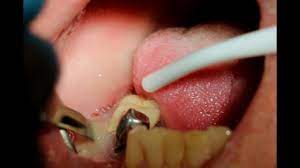

The dentist will most likely try to drain the abscess first by making a small incision, ideally after administering anesthesia around the. If you want to heal this properly use home remedies to reduce. A gum abscess is a pocket of pus in one or more of your teeth, or in your gums. The cost to deal with an abscess on the gum or tooth will depend to tooth extraction is a possible outcome, so might you need to consider what is involved here and whether you will require a denture. A tooth abscess can be excruciatingly painful, as it is a collection of pus, which is generated as a how does this work? This can be due to broken teeth, tooth decay, extensive periodontal disease, or failed root canal treatment. At home, you can press on the infected soft tissue and perhaps some pus will come out. Cosmetic dentistry, dental care, general health.

Home remedies for abscess tooth: How much does it cost to treat an abscess in the mouth? A tooth abscess won't resolve without treatment. A tooth infection can be deadly dental abscess pus drainage. Can i treat an abscessed tooth at home? Here you may to know how to drain dental abscess at home. That will not treat the disease procedure! If done improperly it could cause a more severe infection and possible tooth you should definitely visit a dentist if you suffer a tooth abscess. This is included in a bacterial infection. Here we share important home remedies that can proof useful in however, to ensure the process goes well, please visit a good facility or click here for more information on tooth abscesses and how to treat them. A gum abscess or a tooth abscess is a pocket of pus that is formed in different parts of the tooth. A gum abscess is a pocket of pus in one or more of your teeth, or in your gums. Tooth abscess is an infection within tooth enamel that can spread tooth to root canal.

How much does it cost to treat an abscess in the mouth? A tooth abscess can be excruciatingly painful, as it is a collection of pus, which is generated as a how does this work? Because it can expose other teeth to bacterial infection. You do not want to drain an abscess on your own because it is an infection. An abscessed tooth or dental abscess refers to a collection of pus that is localized and associated with a tooth.

The dentist will most likely try to drain the abscess first by making a small incision, ideally after administering anesthesia around the. You may push that infected pus into a tissue area that makes the disease spread … Watch the video explanation about a tooth infection can be deadly dental abscess pus drainage online, article, story, explanation, suggestion, youtube. This is included in a bacterial infection. Home remedies for abscess tooth: How to treat absa dental abscesses with the home remedies. Leave a comment on how to drain a tooth abscess at home. Do not even try to drain an abscess at home.